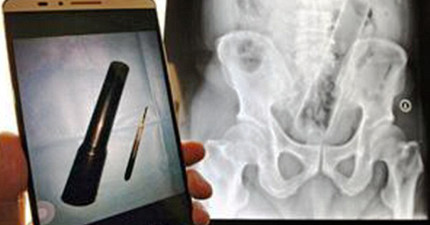

這名男子唱卡拉OK唱到麥克風跑到體內了…

August 13, 2015

世界